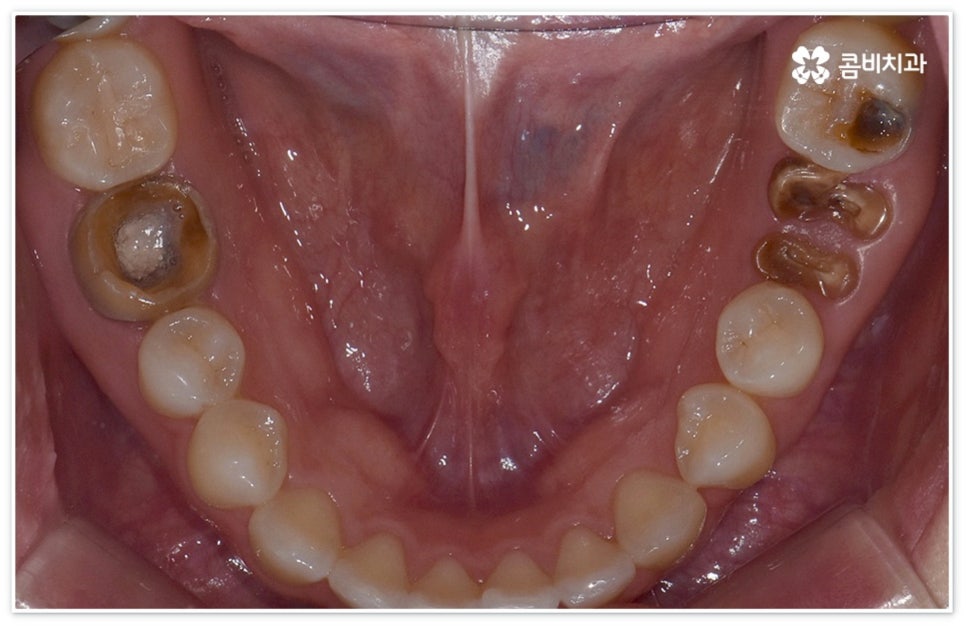

당분을 먹이로 삼아 증식하면서 산성 물질을 만들어내는 박테리아 때문에 치아에 손상을 입게 되는 구강 질환이 충치인데, 겉부분인 법랑질에 막 발생하기 시작했을 때는 해당 부위에 신경이 존재하지 않기 때문에 환자분들의 입장에서 별다른 통증도 느껴지지 않고 겉으로 봤을 때 색이나 모양 등 차이점이 크게 두드러지지 않지만 시간이 지날수록 욱신거리는 통증도 심해지고 색깔도 불투명한 흰색을 지나 점차 갈색, 까만색으로 벌레가 먹은 듯이 보이게 되므로 자각 증상이 있거나 눈에 띄는 변화가 있을 때는 지체하지 말고 치과로 내원하셔서 검진과 치료를 받아보시길 권유드리고 있습니다.

법랑질 안 쪽에는 상아세관이 모여있는데 손상이 이 상아질에 이르게 되면 온도 변화에 민감해지며 음식물을 씹을 때 시큰거리거나 찌릿한 통증을 느낄 수 있어요. 더욱 안쪽으로 세균이 침투하여 신경과 혈관이 모여있는 치수까지 닿게 되면 음식물을 씹지 않고 가만히 있을 때도 통증이 느껴지고 심한 경우 아파서 밤에 잠을 이룰 수 없게 되기도 하는데, 만약 이 시기도 지나치게 되면 치수가 괴사되고 치아 뿌리 끝까지 병소가 침범하여 결국 자연 치아를 살리지 못하고 발치 후 임플란트 시술을 받아야 할 수도 있습니다.

만약 법랑질 또는 상아질 일부에만 충치가 생긴 초기에 이를 발견하고 바로 대처하면 손상이 적기 때문에 우식 부위를 깨끗하게 제거하고 레진 등으로 직접 치료하거나 인레이, 온레이 같은 방식을 통해 간접적으로 보철물을 끼워넣을 때도 좀 더 빠르고 간편한 수복이 가능할 수 있어요. 그러나 바빠서 시간을 낼 수 없거나 또는 약간의 두려움 내지 무심함으로 치과 내원을 미룬 경우 우식 부위가 점차 넓어져 해줘야 할 치료도 더욱 고난도로 복잡해지게 되며 치수 조직까지 되돌릴 수 없는 손상을 입었다면 신경치료가 불가피 할 거예요.